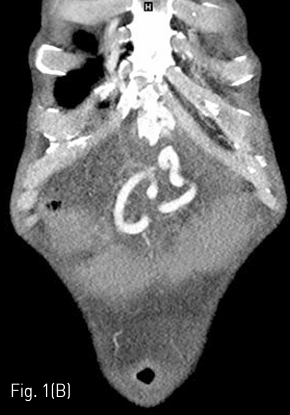

Axial (A) and coronal (B) CT shows large amount of ascites and tortuous dilated vessels between abdominal wall and stomach at access route.

Fig 1B

경피적 영상유도 위창냄술을 시행하기 위해 시술 전 촬영한 복부 컴퓨터단층촬영을 검토하였고, 환자는 간경화로 다량의 복수가 있고, 접근 경로에 문맥 전신 곁가지들로 인한 확장된 혈관들이 관찰되었다 (Fig. 1). 경피적 영상유도 위창냄술을 시행하는 것이 어렵다고 판단하였고 환자에게 Percutaneous transesophageal gastrostomy (PTEG)를 시행하기로 결정하였다.